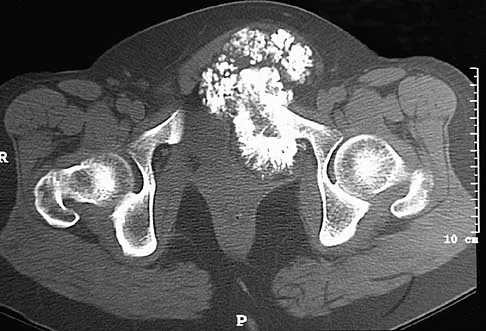

A paraplegic 32-year-old man was pulling himself up in bed by grasping the headboard rails when he felt a pop and immediate pain. A radiograph and CT scan are shown in Figures 2a and 2b. Based on these findings, management should consist of

The coracoid process is an essential component of the superior shoulder suspensory complex and must be maintained. Open reduction and internal fixation is recommended if the fragment is large and displaced more than 1 cm. Froimson AI: Fracture of the coracoid process of the scapula. J Bone Joint Surg Am 1978;60:710-711.